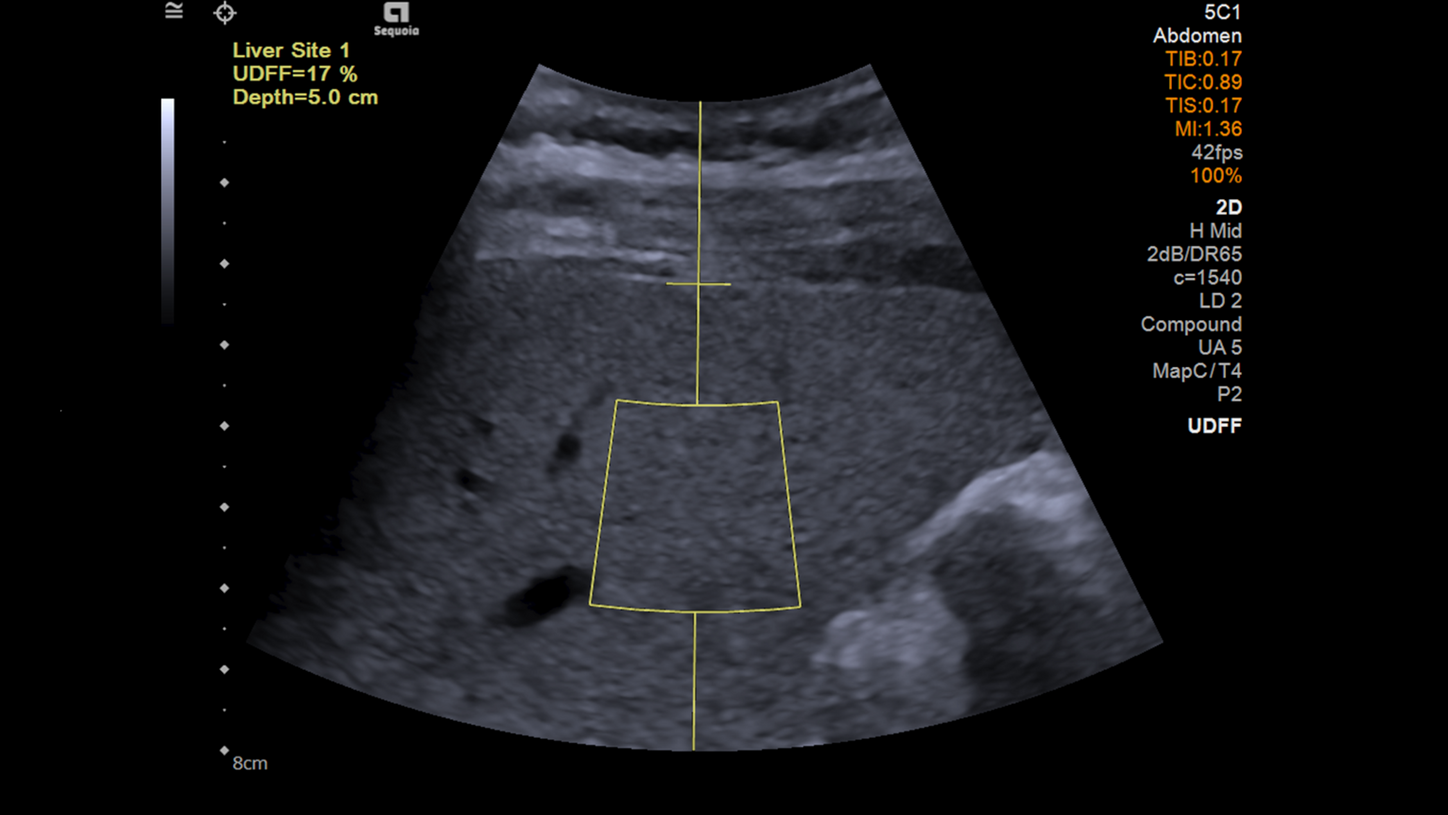

Ermittlung des Leberfettgehalts mit Ultraschall

Die Sonografie ist ein wichtiges bildgebendes Verfahren zur Beurteilung der Steatosis hepatis. In diesem Video mit Dr. Sabine Guth gehen wir auf die Ursachen der Leberverfettung ein und zeigen, wie sie per Ultraschall zuverlässig beurteilt werden kann.

UDFF (Ultrasound Derived Fat Fraction)